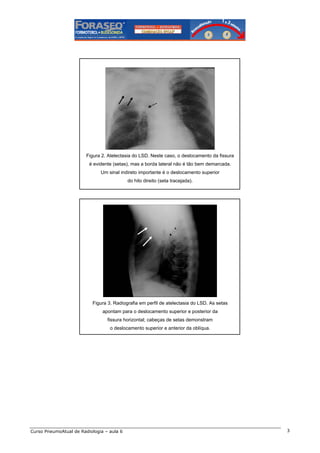

7 – Atelectasia de um pulmão

Figura 8. Atelectasia completa do pulmão direito, com desvio ipsilateral das estruturas

mediastinais. Reparar que na radiografia em perfil apenas uma cúpula

diafragmática (esquerda) é visível (sinal da silhueta).